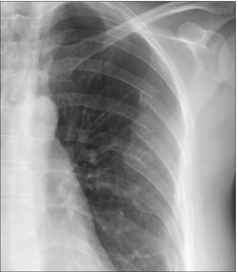

Particular sites need special attention (Figs 32.1-32.3).

Figure 32.1 There is a close relationship between the subclavian artery and the posterior aspect of the first rib and the clavicle. The first rib is very strong. If an injury causes a fracture of this rib then it should be assumed that a very powerful blow has been sustained.

Figure 32.2 Fracture of the first rib and a laceration of the adjacent subclavian artery.

Figure 32.3 RTA. Fractures of the left clavicle, third rib, and scapula. Clearly, a very violent force had occurred. The priority: clinical assessment to rule out a vascular injury.

Double check ribs 1–3, the clavicles, and the scapulae7,8

image A fracture involving ribs 1–3 usually results from a very severe force. Important soft tissue and vascular injuries are potential complications. These include:

image Arterial or venous rupture; arising from the close relationship of the first rib to the subclavian vessels.

image Rupture of a bronchus.

image Brachial plexus injury.

image A fracture of the clavicle or scapula may injure the subclavian artery.